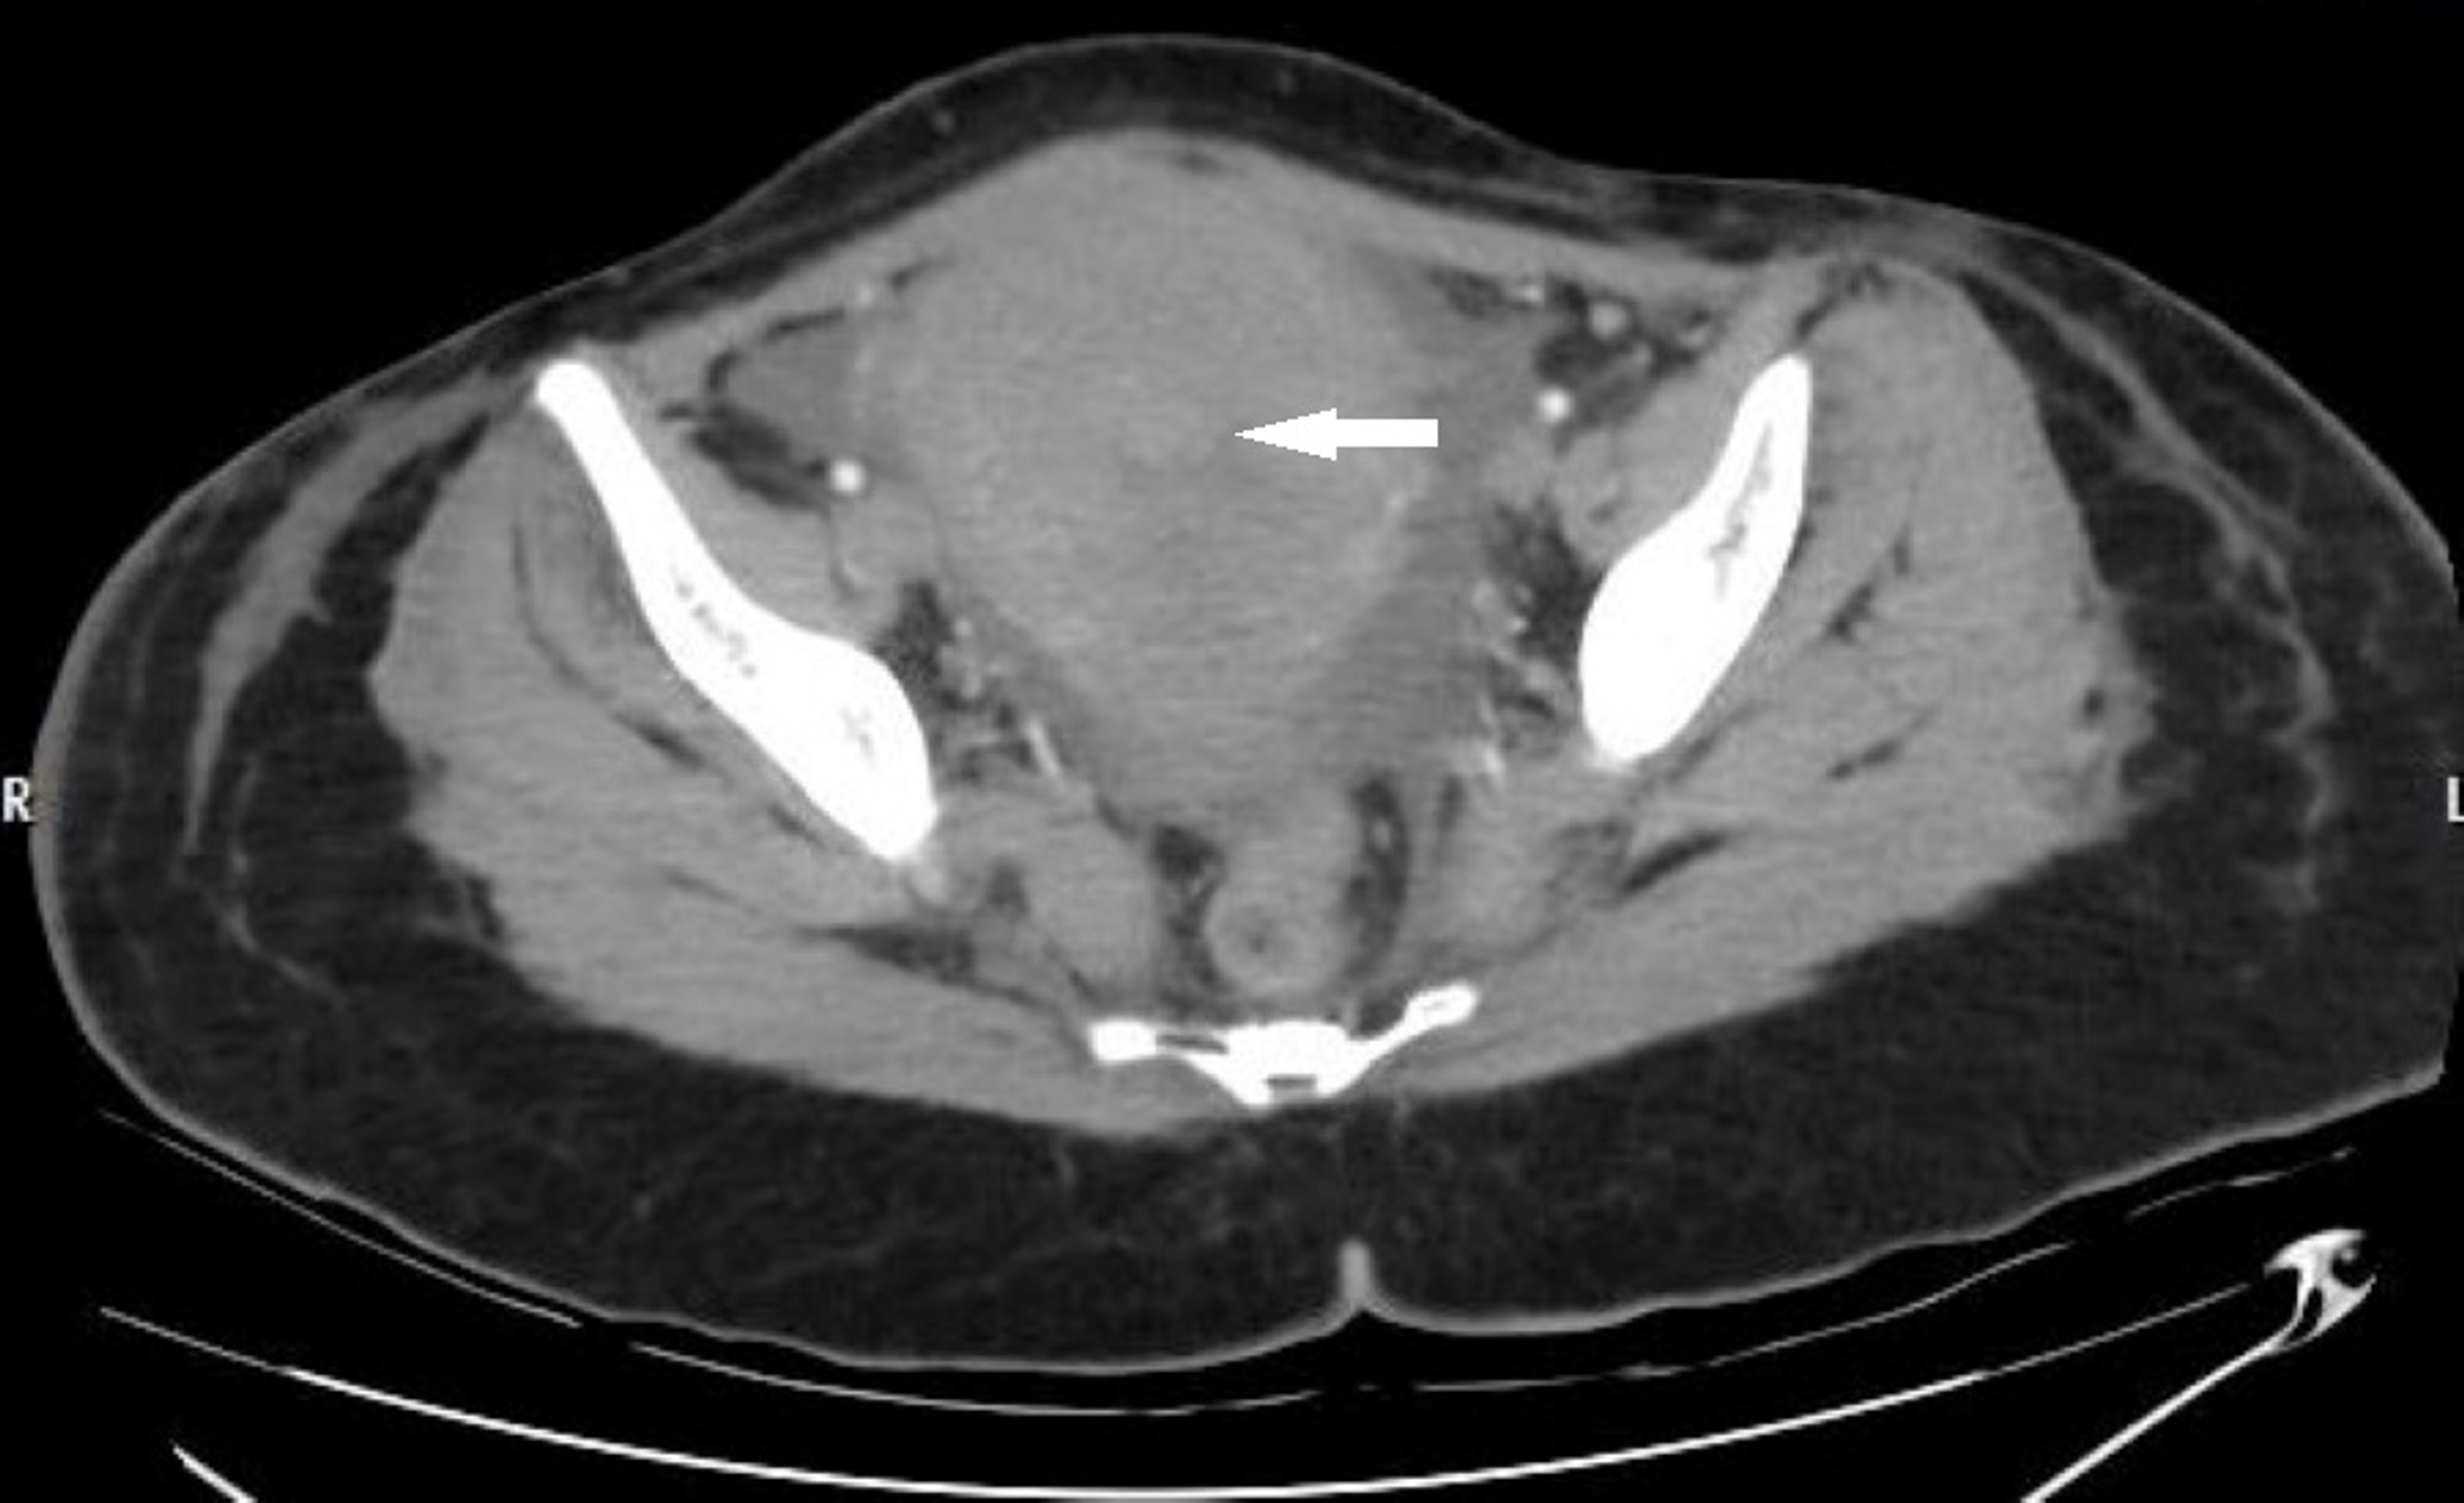

From www.radiology.expert

CT abdomen general Horse Intestinal Perforation The stomach is the most commonly affected. Ideally, cytology should be used to confirm that the horse indeed has intestinal perforation with the finding of intracellular bacteria and lysis of nucleated cells. dilation resulting from small intestinal obstruction is the most common cause. gastric rupture was identified in 8/19 (42.1%) cases, 1/19 (5.2%) had a gi and duodenal. Horse Intestinal Perforation.